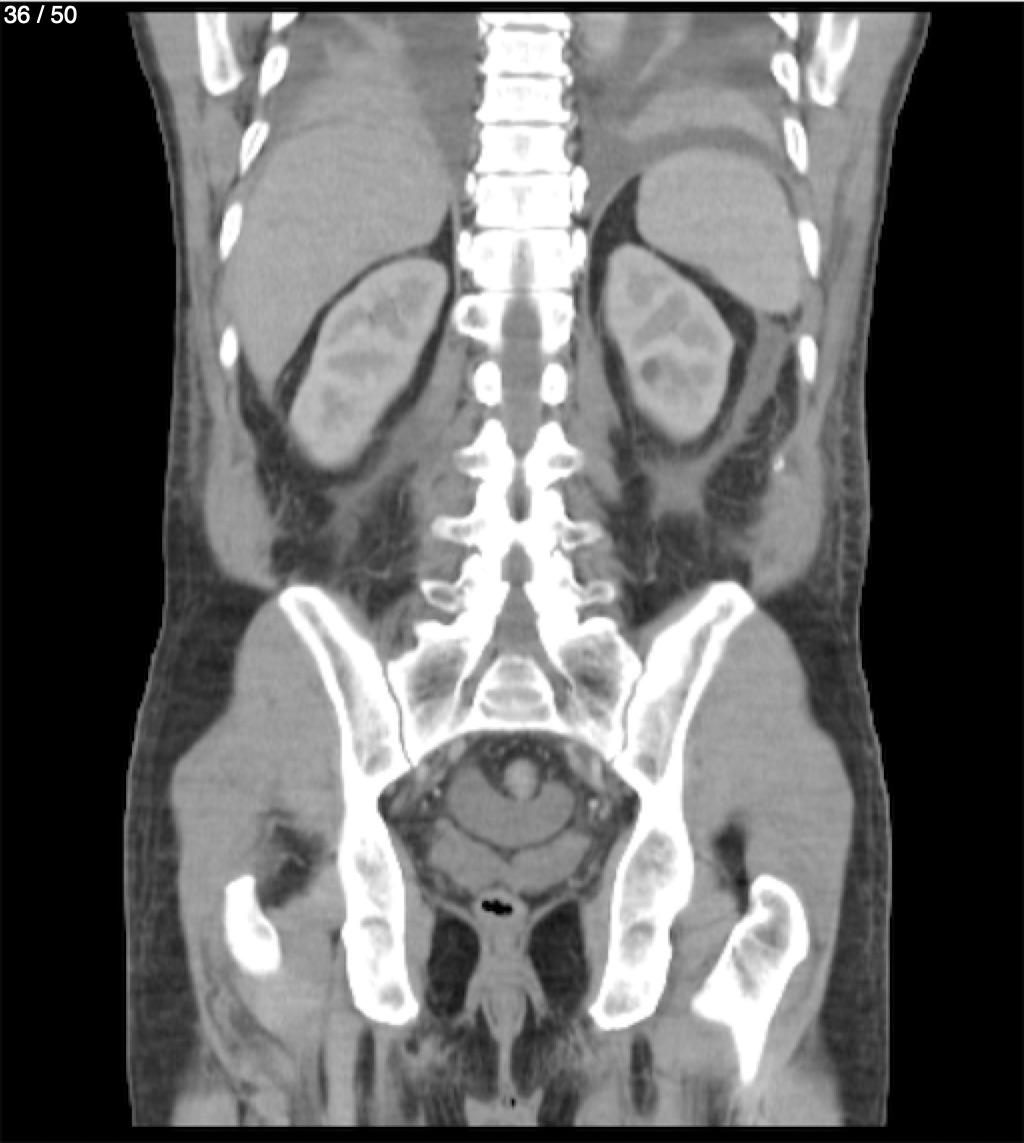

Alonso Victorio Ruiz 62A - T.C Abdomen Syc